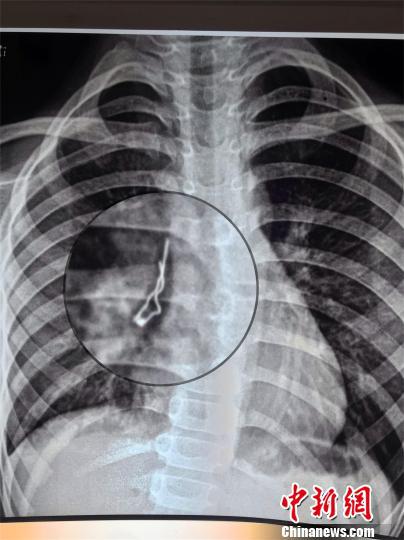

男孩誤吞LED發光二極管 深入支氣管險些扎破肺

中新網武漢6月13日電 (周建躍 溫紅蕾 黃潔瑩)湖北咸寧7歲男孩小路(化名)咳嗽一周不見好,到醫院檢查發現有個不明金屬物體卡在肺部右中間支氣管。湖北省婦幼保健院兒內科醫生12日通過手術取出一個LED發光二極管,幸好該二極管是尖頭朝上沒有扎穿肺。

原來,小路吞下去的是個LED發光二極管,長約2.6厘米,寬7毫米。醫生介紹,這個二極管在小路肺里呆了一周,幸好鐵絲頭朝上,沒有扎穿肺。如果鐵絲朝下,隨著呼吸運動,尖頭隨時有可能刺傷氣管,引起肺部出血或者氣胸等嚴重的致死性并發癥。

男孩誤吞LED發光二極管 深入支氣管險些扎破肺LED發光二極管卡在小路肺部右中間支氣管。院方供圖